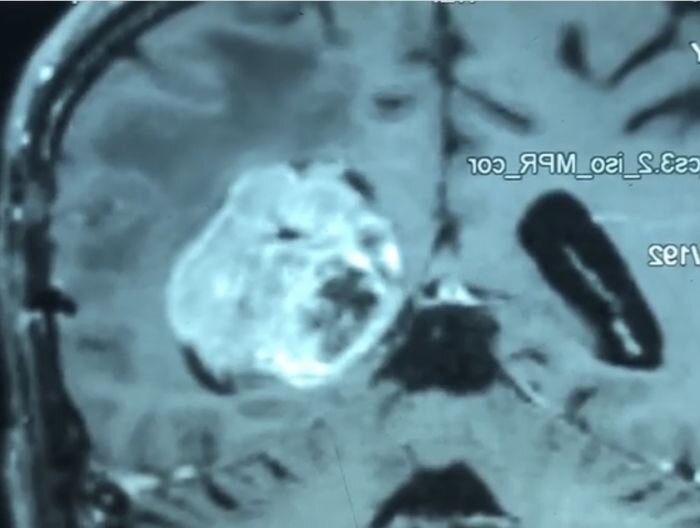

Tumors of the third ventricle of the brain

Tumors of the lateral ventricle of the brain

Epidermoid cysts of the brain

Neuroma of the bridge-cerebellar angle

Extracranial tumors of soft tissues of the head

Radiotherapy of primary tumors and secondary metastatic lesions of the brain